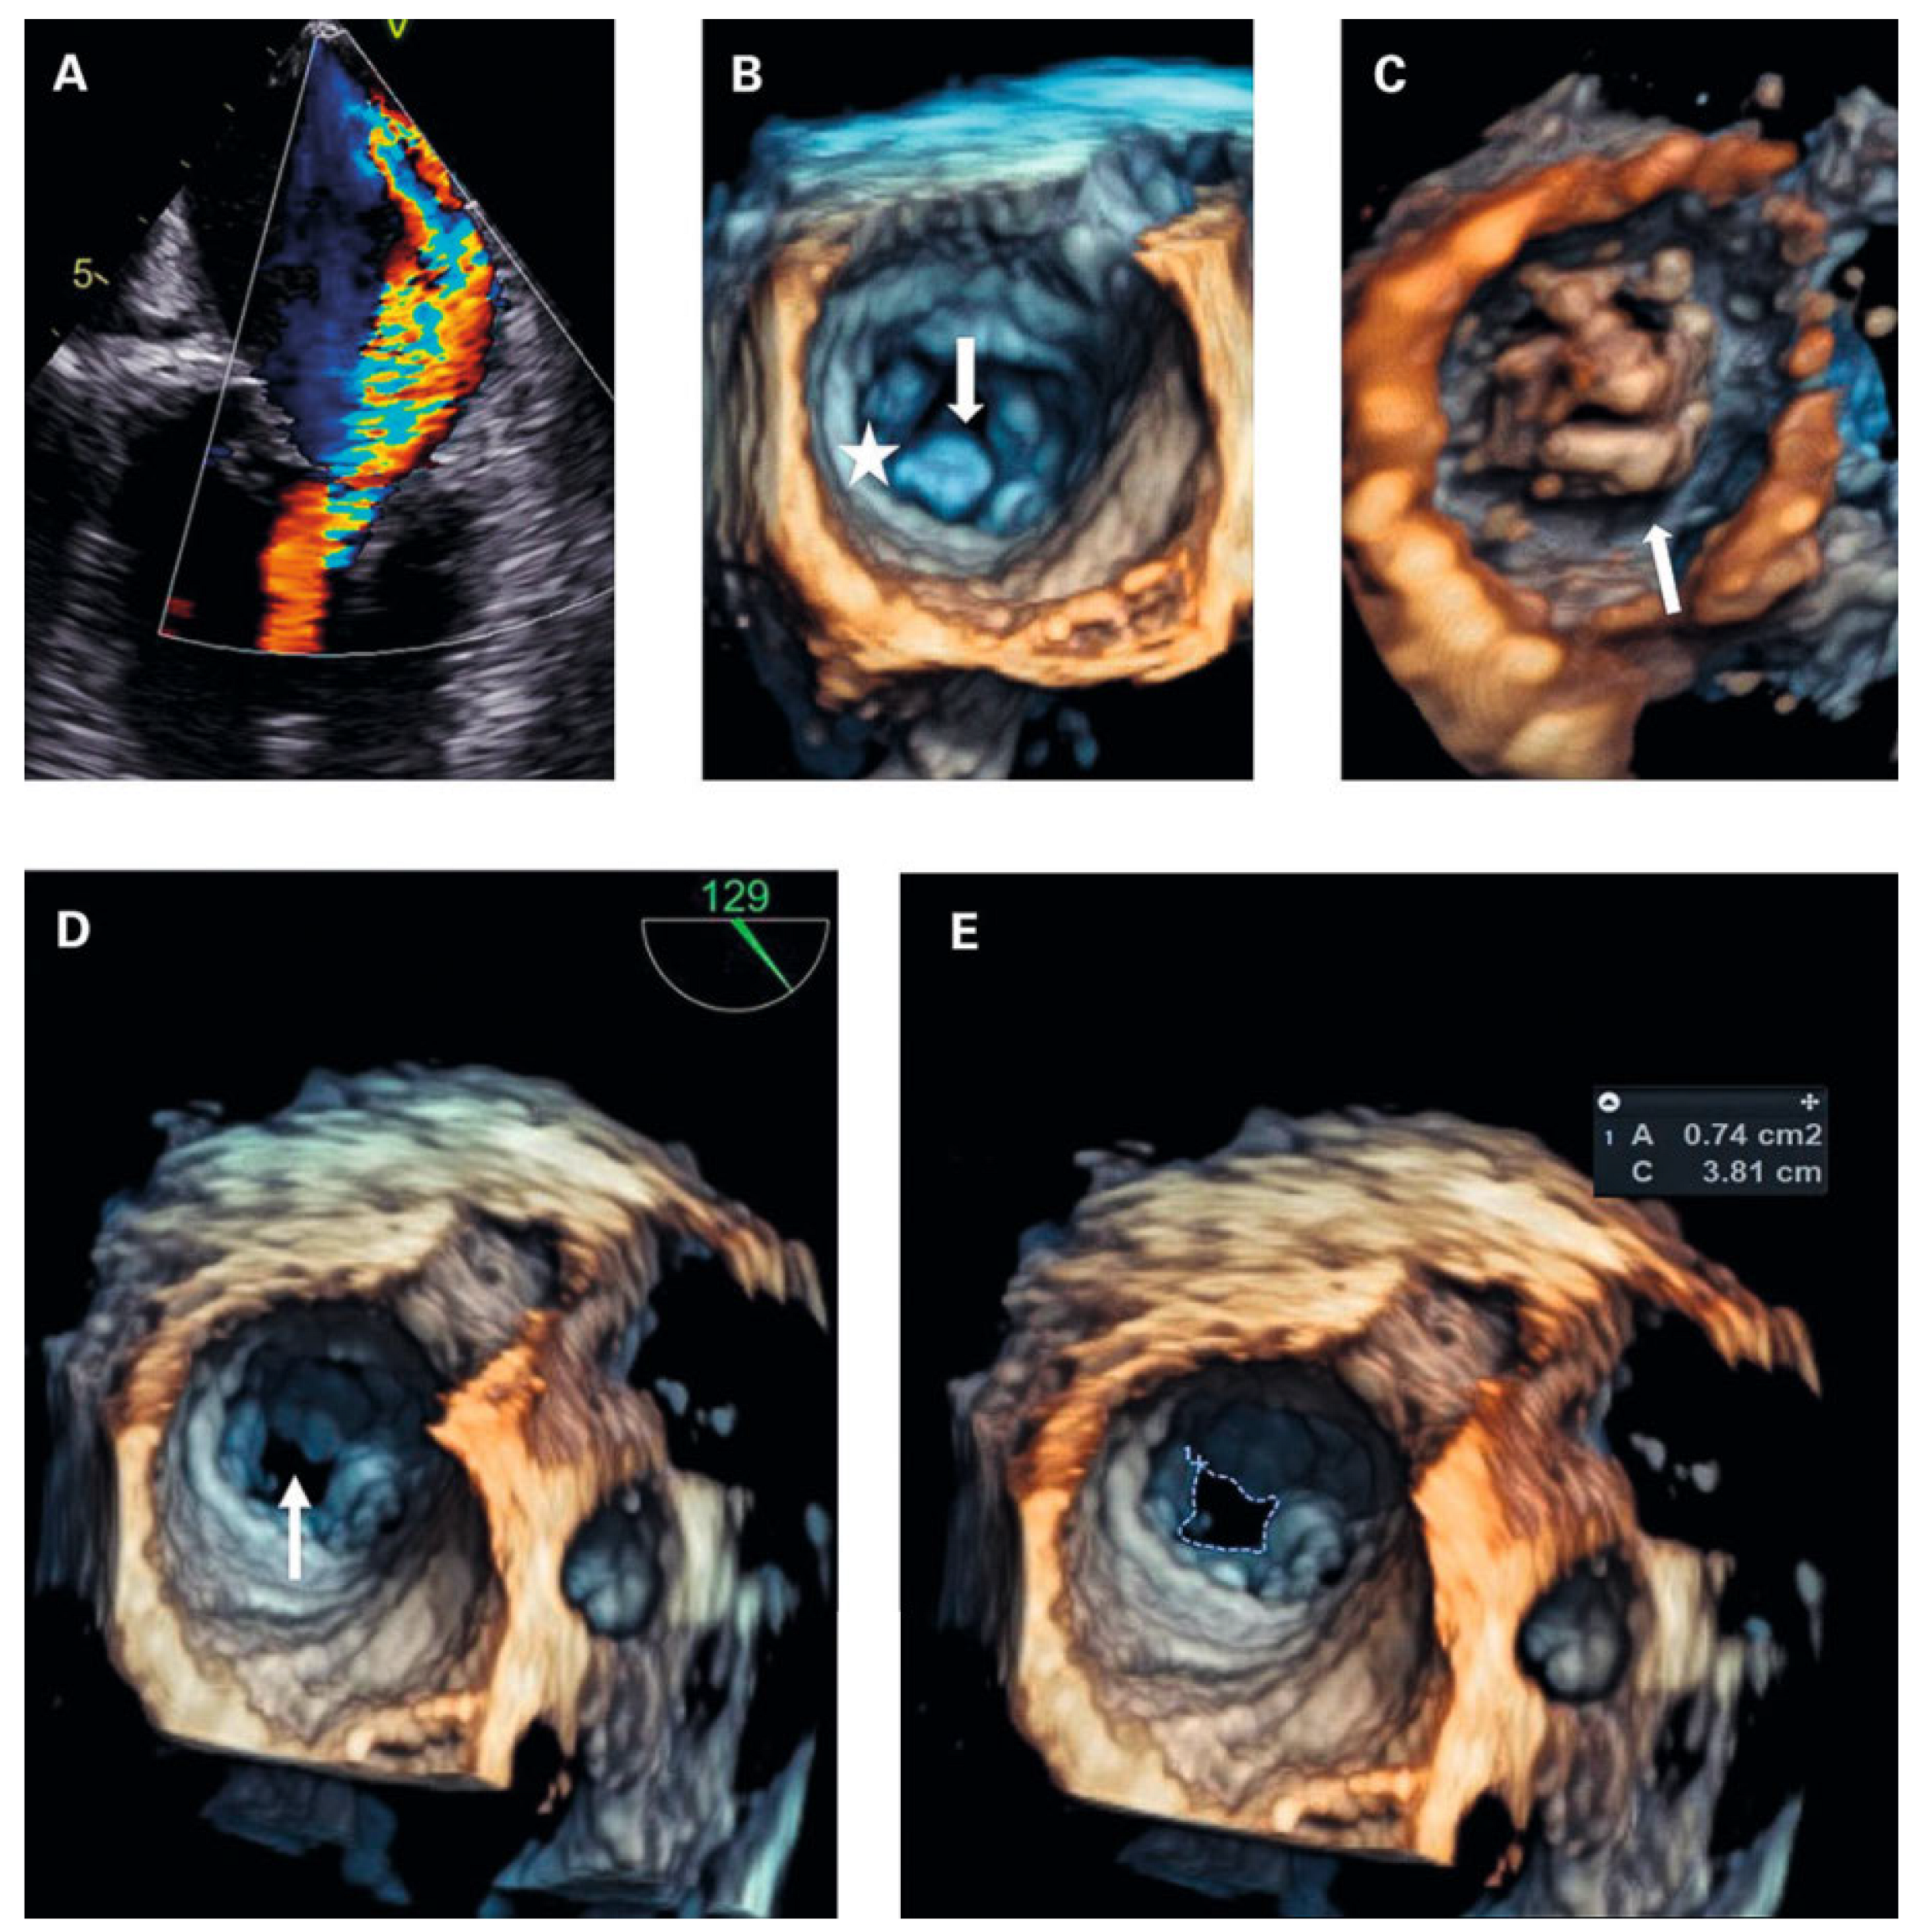

To exclude left-heart disease as a possible cause of the congested bronchial vessels and the alveolar haemorrhage syndrome, first transthoracic and later transoesophageal echocardiography were performed. The main finding was a grotesque doming of thickened mitral leaflets with a severe subvalvular mitral stenosis (transthoracic echocardiography figure 3A–F and transoesophageal echocardiography figures 4A–D; mean pressure gradient 16.2 mm Hg, reference <5 mm Hg, at a heart rate of 82/min, calculated mitral valve area by pressure half-time method 1.3 cm2, reference >1.5 cm2; figure 3f; planimetry of mitral valve area 0.74 cm2 in TOE approach, figure 4d+e) and severe mitral regurgitation with pulmonary vein backflow due to restricted leaflet motion (fig. 4a). The right ventricular / right atrial pressure gradient across the tricuspid valve could not be obtained.

Transthoracic and transoesophageal 4D imaging revealed extensive fusion of thickened and shortened chordal structures extending down to the papillary muscles, a shortened posterior leaflet and a prolonged and entirely thickened anterior leaflet with restricted mobility, and mild calcification (fig 3 and fig 4), adding up to a Wilkins Score of 13 points (range 4–16).

Figure 4. (a) transoesophageal echocardiography (tOe, 30°): Colour doppler revealed severe mitral regurgitation, which was not apparently visible in transthoracic echocardiography. (B) 4d tOe (surgical view at diastole) showing normal valve orifice at valvular level. Arrow subvalvular thickening. Asterisk posterior mitral valve annulus. (C) 4d tOe (ventricular view at diastole) visualising extensive thickening of the subvalvular apparatus as cause of stenosis. (D) 4d tOe surgical view of stenotic mitral valve area (arrow). (e) 4d tOe planimetry of mitral valve area from surgical view.